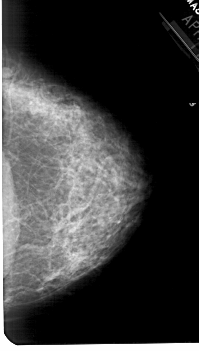

A_1777_1.LEFT_CC

LEFT_CC LINES 4966 PIXELS_PER_LINE 2911 BITS_PER_PIXEL 12 RESOLUTION 43.5 OVERLAY